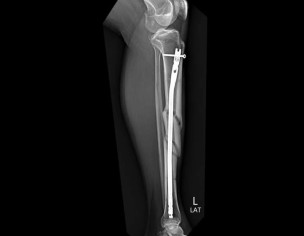

aoa please dr tell me when it will b healed . 5 march 2023 opreation . now october how many time to take to heel completly . age patient 47 years. patient got accident in january both legs are damag right leg is most damage and then in feb right leg amputed above knee . this is left leg x ray . want to ask how many time to take heeling completly. please tell me in how many time to take complete heeling

Xrays show good healing. Is the patient walking? Ask the patient to walk stick or crutch on right side. The more the patient walks on this left leg, the better remodeling there wiil be. In short, patient can walk on left leg

your injury is a severe and operation done very well you start to weight beering on th injured leg wait 18 to 24 months for full recovery